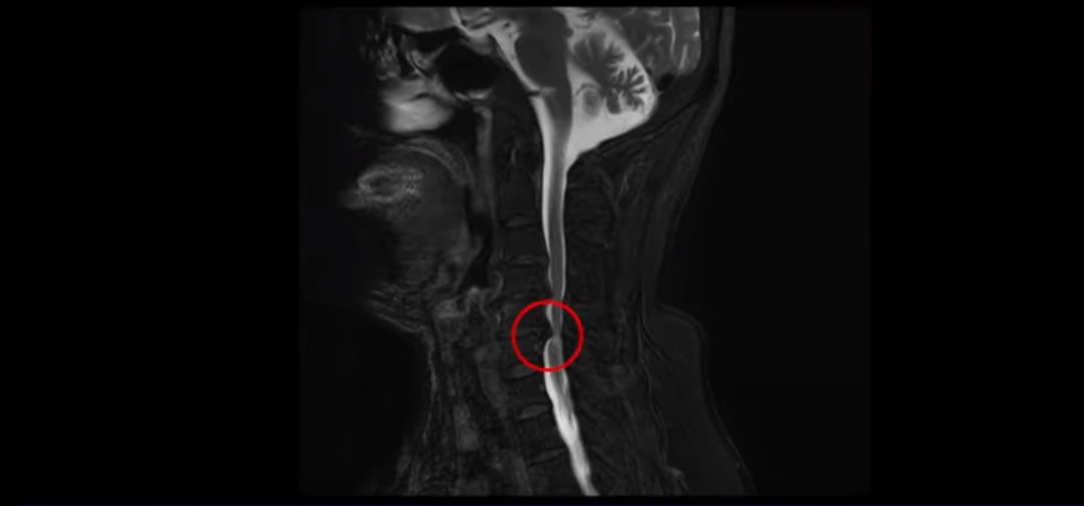

양손 마비와 보행 시 균형을 못 잡고 비틀거리는 환자분의 MRI 상태 및 증상은?

이 환자분은 목디스크 5번, 6번에 심한 디스크로 인해 경추척수증이 발생한 환자입니다. MRI에 보시는 것처럼 디스크가 심하게 밀려나와 이로 인해 척수신경이 눌려 신경손상이 하얗게 보입니다.

환자분의 증상은 양쪽 손, 특히 손바닥에 다 마비가 오고 다리 힘이 빠져 균형을 잡지 못해 비틀거리며 잘 걷지 못하셨습니다. 이는 경추척수증의 전형적인 증상입니다. 대학병원에서도 별다른 구체적인 설명 없이 무조건 수술해야 한다는 말을 듣고 저희 모커리한방병원에 내원하셨습니다.

경추척수증은 뇌에서부터 나와 목을 통해 전신으로 내려가는 중추신경인 척수가 목디스크, 골화된 후종인대, 경추 협착으로 인해 심하게 눌려 손상이 생기는 질환입니다. 그렇기 때문에 감각기능, 운동기능 저하 등의 증상이 발생합니다. 뿐만 아니라 양손, 팔 등에 통증은 물론 저리는 증상이 나타나고 손의 움직임이 둔해지며 다리 근력도 약화돼 힘이 빠집니다. 또한 균형을 잘 잡지 못해 걸음을 휘청거리는 등 보행장애 증상이 나타나기도 합니다.